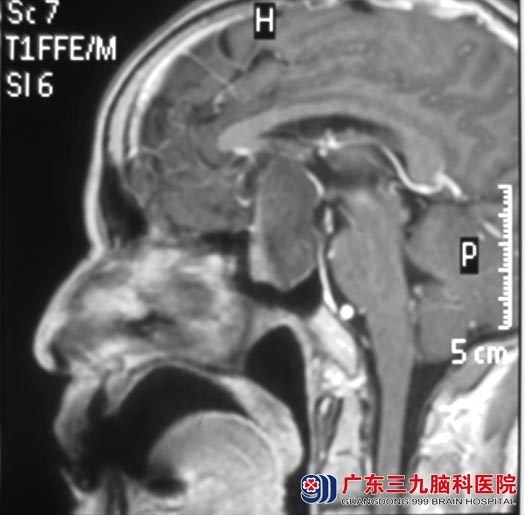

一周前突发头痛,额部胀痛,疼痛时视力模糊加重,夜尿增多。当地医院的头颅CT检查提示鞍区病变,进一步头颅MR检查考虑颅咽管瘤可能,待排垂体腺瘤。

广东三九脑科医院垂体瘤诊疗中心 鲁明主任查体发现,丘先生双眼颞侧视野及右眼上、下视野缺失,心电图结果提示窦性心动过缓,腹部B超结果提示肝囊肿,结合影像检查考虑肿瘤卒中,阿托品试验后经心内专家会诊排除病窦综合症,考虑可以耐受手术。http://www.999brain.com/

▲手术前